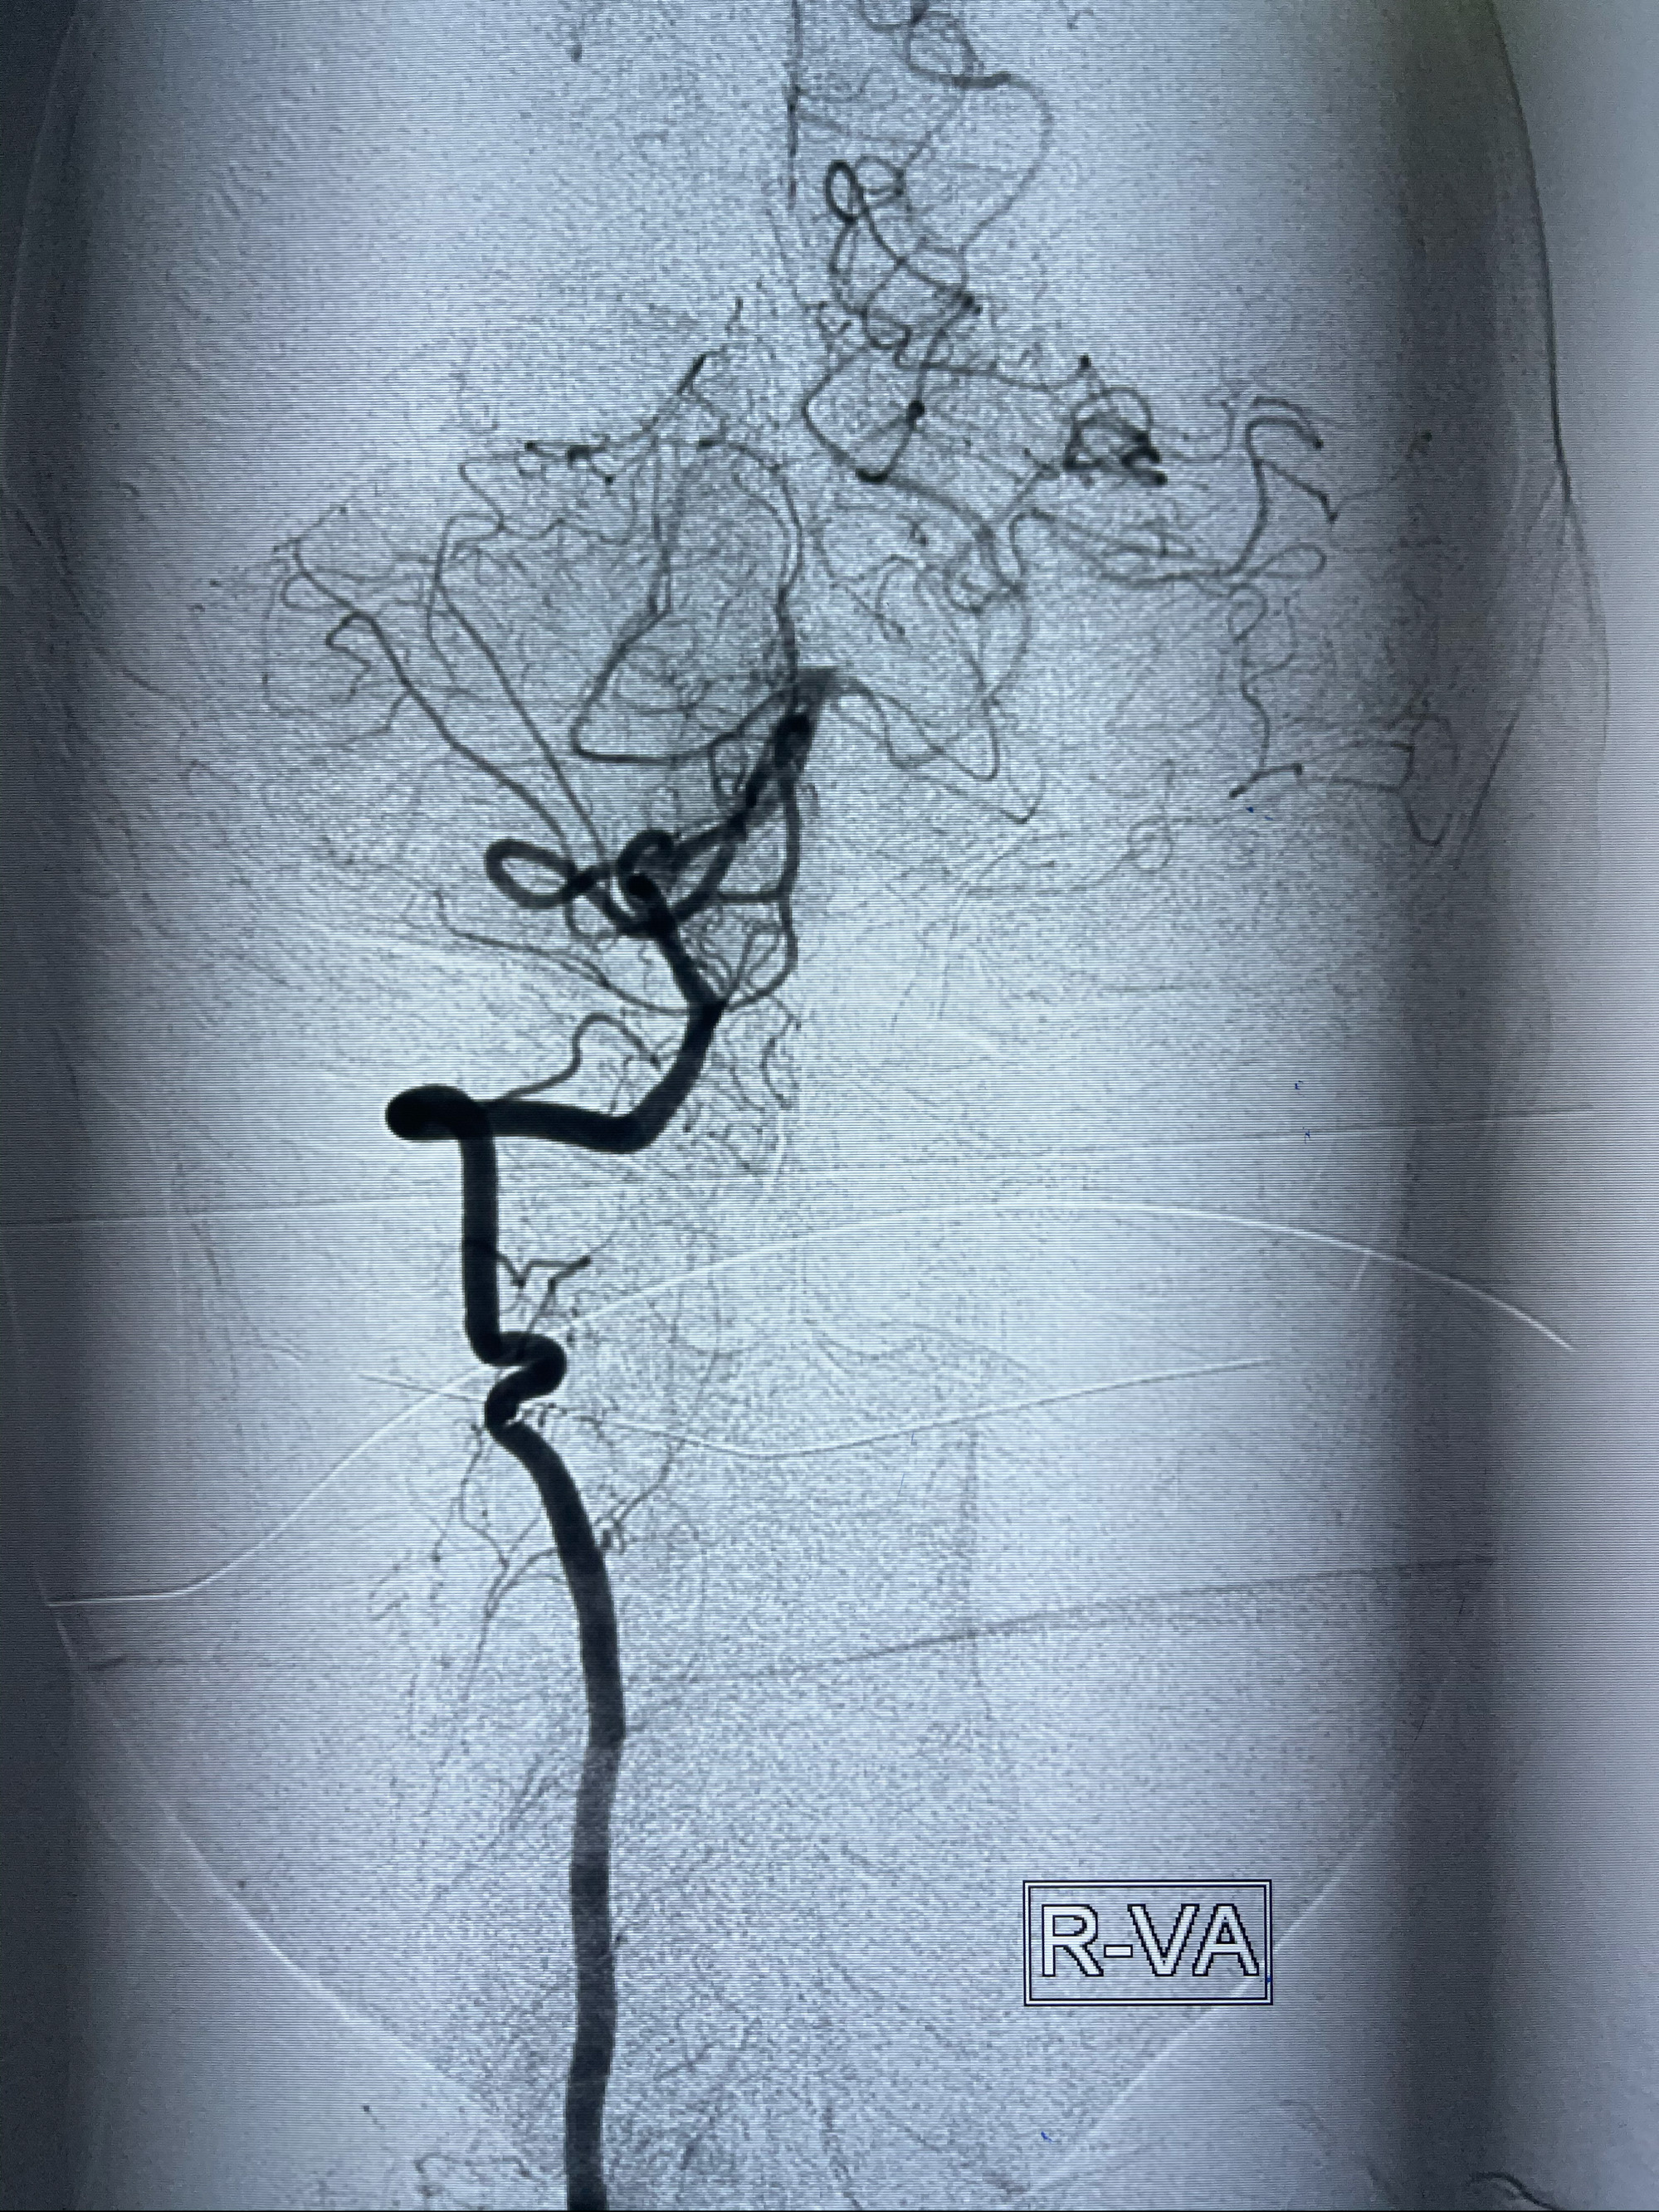

左侧椎动脉V4夹层动脉瘤多支架辅助栓塞:

1.Enterprise4.0-23mm;

2.Tubridge3.5-30mm密网支架

DA导引导管到位

工作角度造影

Eterprise4.0-23mm支架导管到位

Echelon10 45°角微导管塑形后到位

8mm-40cm微弹簧圈成篮

即刻造影

支架到位

支架释放,透视下